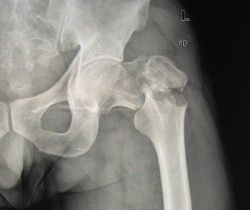

股骨頸骨折按股骨頸骨折部的形態分為嵌入型和錯位型骨折。這兩型股骨頸骨折的骨折線可表現為緻密線和/或透亮線。緻密骨折線表示兩骨折端的骨小梁有重疊嵌插,而透亮骨折線則意味著兩骨折端有分離。嵌入型股骨頸骨折無明顯錯位,通常股骨頸可見模糊的緻密骨折線,局部骨小梁中斷,局部骨皮質出現小的成角或凹陷,股骨幹的外鏇畸形小明顯。此型骨折屬較穩定性骨折。由於骨折發生時外力作用的不同,股骨頭可發生不同程度的內收、外鏇。前傾或後傾的成角畸形。如出現嵌入端成角畸形較明顯,或骨折線的斜度較大、骨折端部分有分離,或股骨幹外鏇明顯時,提示骨折不穩定。

錯位型股骨頸骨折較常見,亦稱為內收型股骨頸骨折。兩折端出現鏇轉和錯位。股骨頭向後傾骨折端向前成角,股骨幹外鏇向上錯位,骨折線分離明顯。另外,接骨折部位又可分型為:頭下型:骨折線位於頭頸交界處;經頸型:骨折線位於股骨頸的中段;基底型:骨折線位於股骨頸底部,大部分位於關節囊外;頭頸型:骨折線上端在頭下,下端在股骨頸的中部,此型骨折近端的血供不好,不易癒合。